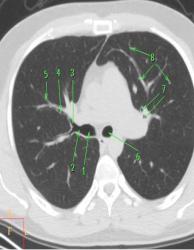

Рис. 25. КТ на уровне нижней части

корней легких в легочном электронном окне:

1 – поперечное сечение левой ЛА; 2 – поперечное сечение правой ЛА;

3 – левая нижняя легочная вена; 4 – правая нижняя легочная вена;

5 – поперечное сечение левого нижнедолевого бронха; 6 – поперечное сечение

промежуточного бронха правого легкого; 7 – грудная аорта

Рис. 26. КТ на уровне базальных

сегментов легких в легочном электронном окне:

1– сечения сосудов легких;

2– поперечные сечения сегментарных бронхов;

3– тонкая полоска листков плевры по ходу главной междолевой борозды